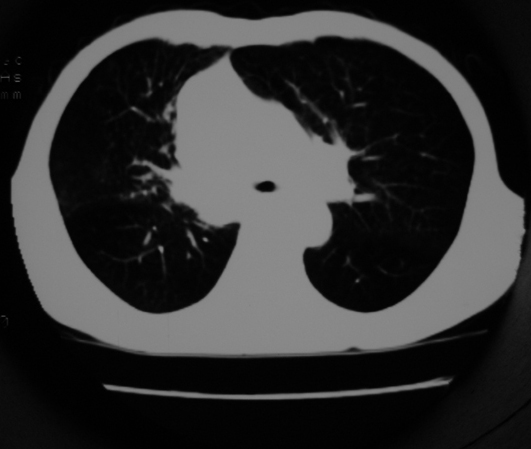

以下是引用同在2007-1-27 14:13:00的发言:[br]支持右侧中央型肺癌伴阻塞性病变.

以下是引用zjzjr在2007-1-27 16:56:00的发言:[br]支持右肺中心型肺癌伴阻塞性肺炎.